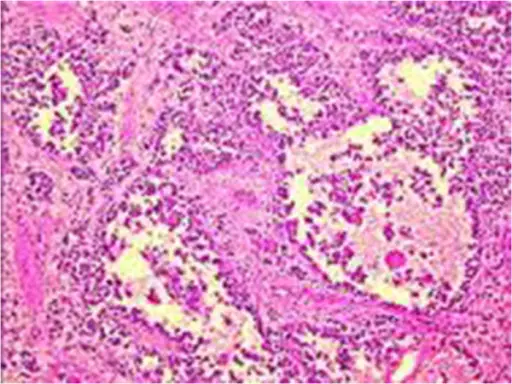

Liposarcoma

Liposarcomas are malignant tumors of adipose tissue.

Liposarcomas are very rare compared to lipomas (their benign counterparts).

Liposarcomas may metastasize.

Adults are more commonly susceptible to developing liposarcomas compared to children.

Definitive diagnosis of liposarcoma is made by pathology showing malignant proliferation of adipose tissue.

Lipoblasts are the characteristic cells seen in liposarcoma.

Treatment of liposarcomas involves surgical excision.